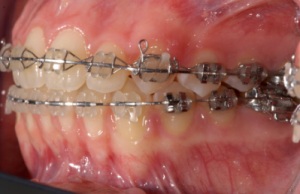

Metallbrackets

Keramikbrackets